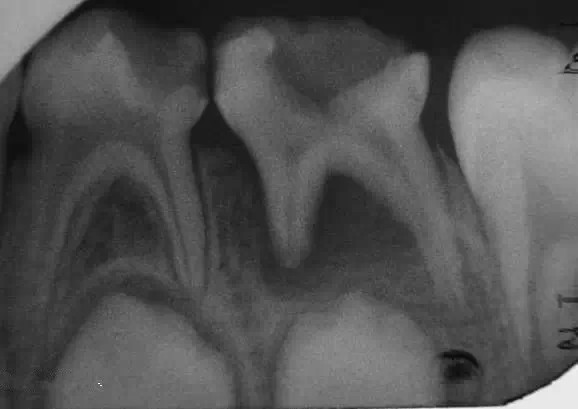

1.jpg

乳牙根尖周病是指根尖周圍或根分叉部位的牙骨質(zhì)、牙周膜和牙槽骨等組織的炎癥性疾病,其病因和臨床表現(xiàn)均有其特點(diǎn)。(引自醫(yī)科大 課件)

乳牙牙髓壞死的診斷很重要!

A,如果小孩子以前的牙痛癥狀不是很明顯或是說不清楚,在檢查時(shí)又不會(huì)痛,就有可能忽略了乳牙牙髓的診斷。

B,乳牙慢性根尖炎癥,往往可有潛在的細(xì)小的瘺孔或是已經(jīng)處于半閉合狀態(tài)的瘺管,而周圍并無明顯的炎癥的,存在局部牙齦淤血的,很容易被忽略。

C,如果按照一般深齲洞而直接充填的,填補(bǔ)以后非常容易發(fā)生急性根尖周炎癥,形成齒槽膿腫。

D,在臨床上,有時(shí)看到的齲洞不深,又沒有穿髓孔,但細(xì)菌及其毒力可能已經(jīng)進(jìn)入牙髓,造成(導(dǎo)致)牙髓的壞死。

總結(jié)一下,1,在決定牙髓治療前一定要拍個(gè)X光片。有助于后續(xù)治療。